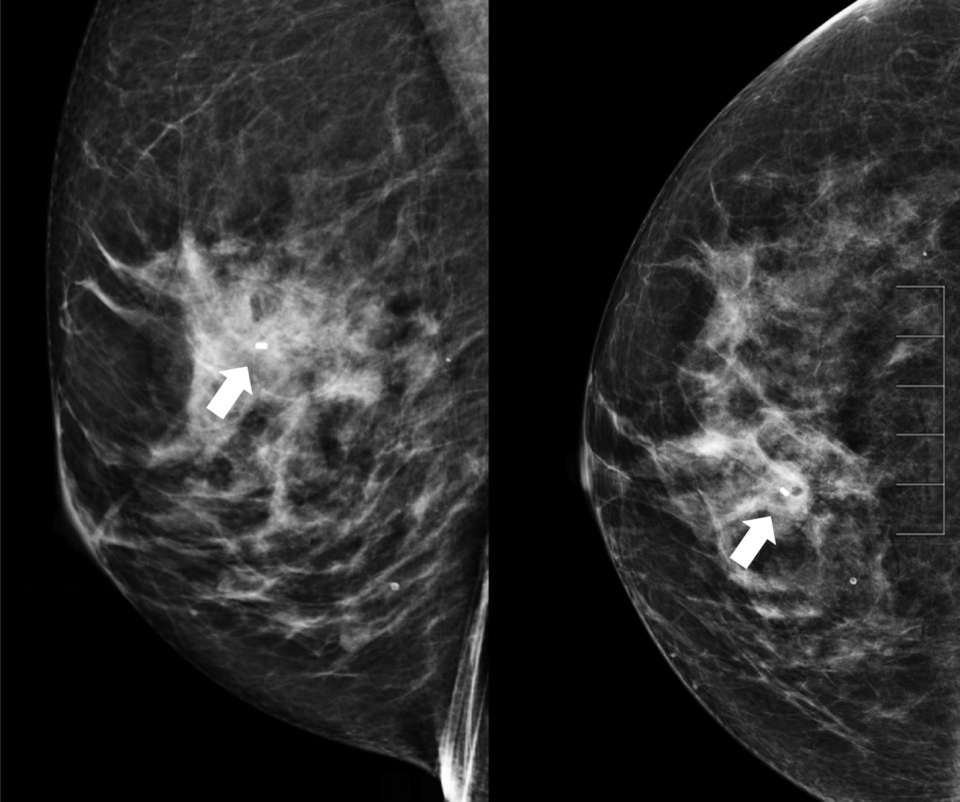

• Radiologist confirms appropriate compression of breast tissue, appropriate visualization of biopsy target, and performs adjustments if necessary (Figure 1).

Figure 1. Craniocaudal (CC) tomosynthesis scout image of the right breast shows coarse heterogeneous calcifications measuring 5 mm with grouped distribution at 12 o’clock at middle depth located 4 centimeters from the nipple (arrow).